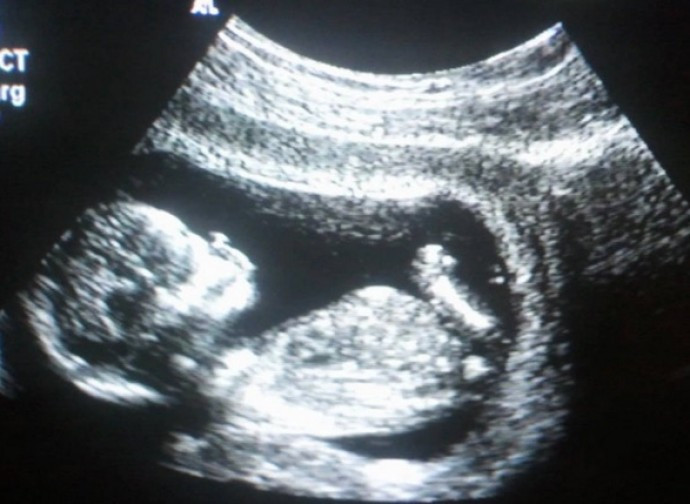

Il Ministero della Salute ha presentato il suo rapporto annuale sullo stato di attuazione della legge 194: 65.746 gli aborti ufficiali nel 2023. Nuovo record per la vendita dei “contraccettivi d’emergenza”, responsabili di innumerevoli cripto-aborti.

E di aborto si continua a morire a decine di migliaia anche in Italia, come ci racconta l’annuale rapporto del Ministero della Salute sullo stato di attuazione della legge 194. Secondo la relazione ministeriale nel 2023 sono stati effettuati 65.746 aborti. È come se la città di Fano fosse sparita nel nulla. C’è un leggerissimo incremento dello 0,1% rispetto al 2022. Il tasso di abortività, che è il numero di aborti per 1.000 donne in età fertile ed è il dato più significativo, è fisso rispetto all’anno precedente al 5,6: dunque quasi 6 donne su mille hanno abortito nel 2023. La relazione ci informa che la procedura abortiva più scelta è quella chimica che nel tempo sta riscuotendo purtroppo sempre più favore tra le donne e a monte tra i medici, dato che sono loro a consigliarla: il 59,4% del totale degli aborti è stato effettuato con la RU486, procedura che, grazie all’ex ministro Speranza, prevede, contra legem, la somministrazione della prima pillola in day hospital e l’assunzione a casa della seconda con l’evacuazione del figlio tra le pareti domestiche o in ufficio, in tram, etc., insomma laddove si trova la madre.